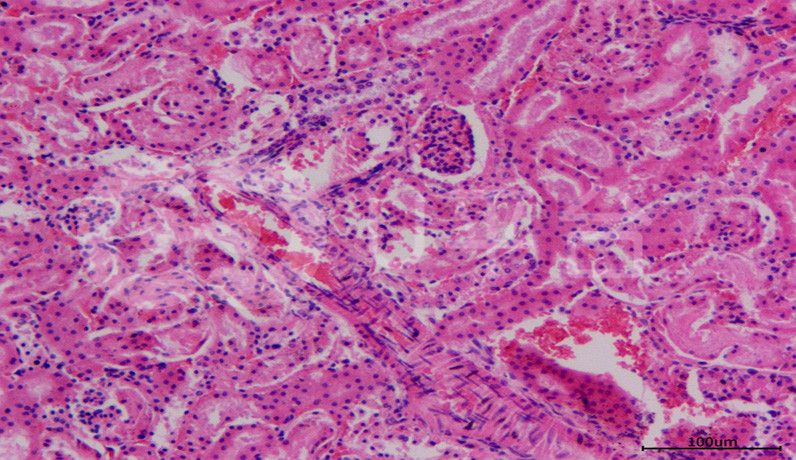

HE染色常見問題與處理方法由普拉特澤生物總結分享。一張優質的HE染色切片,應該具備切片完整、無皺褶、細胞核著色清晰呈藍色、細胞質呈鮮紅色、核仁核膜核內染色質顆粒清晰等特點,但多數切片染色新手即使是照書操作,仍然是破綻不斷,慘不忍睹。普拉特澤生物病理實驗平臺在承接大量的HE染色代做實驗后,積累豐富的操作經驗,染過多種動植物、菌類組織樣本,總結了HE染色時常見的各種常見問題與解決方法。一起來看看吧!